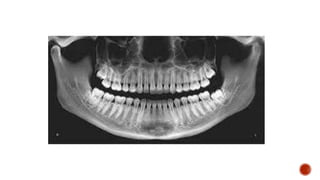

 AP and lateral radiographs of the skull show a well defined lytic lesion involving

the left ramus of the mandible causing scalloping of the medial margin with

associated soft tissue swelling.

 The patient is stationary, while the x ray source and the film rotates.

 sitting/standing completely upright

 head immobilized and on a chin rest

 biting down on a radiolucent bite block

 tongue against the hard palate